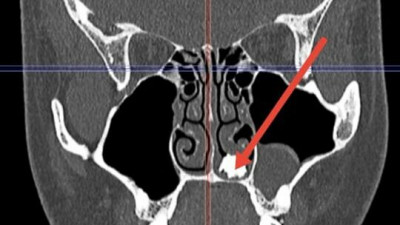

В Долгопрудненскую больницу обратился 22-летний молодой человек с жалобами на затяжной насморк. Обследование, проведенное врачами, выявило плотное костное образование в носовой полости пациента.